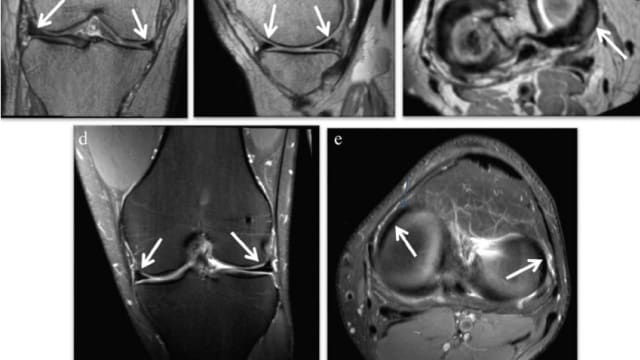

Rund sechs Jahre später, im Januar 2019, hatte der Mann mit Jahrgang 1970 erneut Kniebeschwerden. Es wurde eine Meniskusläsion am linken Knie festgestellt. Sein behandelnder Orthopäde sah die Ursache dafür in der Knieverletzung vom Januar 2013. Die Axa verneinte allerdings eine Leistungspflicht. Auch das Verwaltungsgericht des Kantons Thurgau sah keinen Zusammenhang zwischen den beiden Ereignissen.